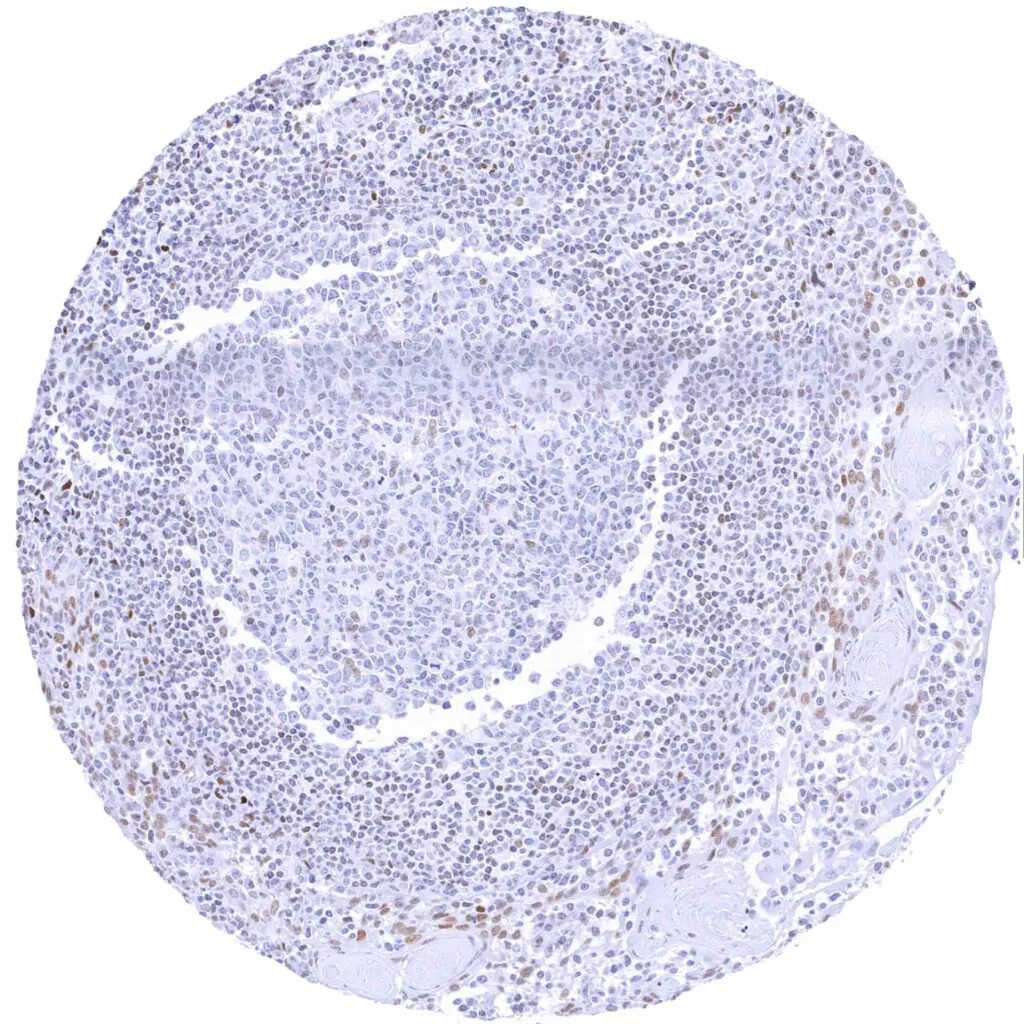

Lymph node – Weak to moderate TLE1 staining in a subset of lymphocytes, predominantly in germinal centres